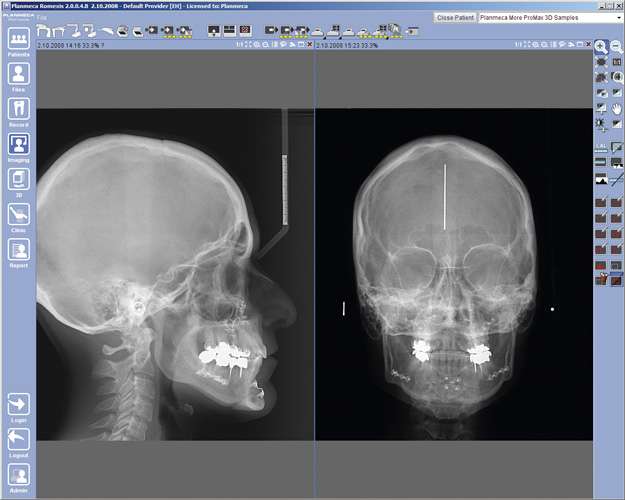

Digitale Volumentomographie (DVT) ist eine Röntgen- Bildgebungstechnologie, bei der auf einer Kreisbahn einzelne Projektionsaufnahmen eines Patienten aus unterschiedlichen Winkeln aufgenommen werden. Ein volumetrisches 3D-Bild der abgebildeten Region wird aus diesen 2D-Projektionen errechnet. Die daraus resultierende isometrische Ortsauflösung im Volumen kann mit unserem fortschrittlichen Bildbearbeitungsprogramm aus jedem Winkel in der axialen, koronalen und sagittalen Querschnittsebene betrachtet werden.